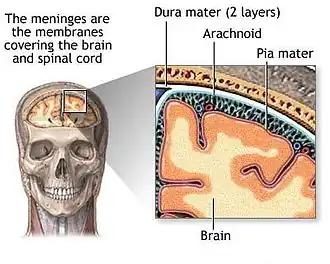

Meninges

Human brains are surrounded by a system of connective tissue membranes called meninges that separate the brain from the skull. This three-layered covering is composed of (from the outside in) the dura mater, arachnoid mater, and pia mater. The arachnoid and pia are physically connected and thus often considered as a single layer, the leptomeninges. Between the arachnoid mater and the pia mater is the subarachnoid space which contains cerebrospinal fluid (CSF). This fluid circulates in the narrow spaces between cells and through the cavities in the brain called ventricles, to support and protect the brain tissue. Blood vessels enter the central nervous system through the perivascular space above the pia mater. The cells in the blood vessel walls are joined tightly, forming the blood–brain barrier which protects the brain from toxins that might enter through the blood.[35]

Tumors of the meninges are meningiomas and are often benign. Though not technically a tumor of brain tissue, they are often considered brain tumors since they protrude into the space where the brain is, causing symptoms. Since they are usually slow-growing tumors, meningiomas can be quite large by the time symptoms appear.[36]